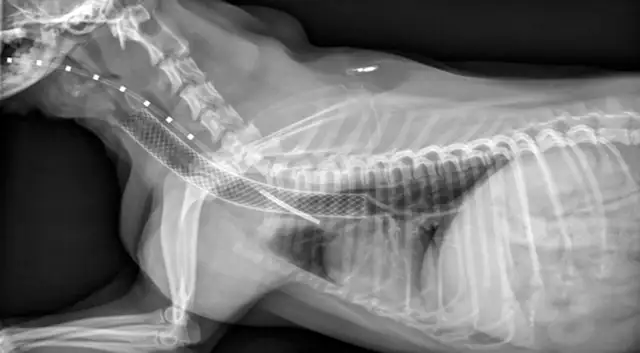

Patients are recovered in an oxygen cage and monitored for signs of respiratory distress. They are sent home on a tapering dose of corticosteroids, 2 weeks of antibiotics, and client instructions to administer sedatives and antitussives as needed. In one study of 18 dogs, the mortality rate was 11.1% within 60 days after stent placement; however, long-term improvement was observed in the remaining dogs.22 Stress, excitement, and exercise need to be limited for 4 weeks. Patients should be reevaluated (ie, examination, survey radiography) at 1, 3, and 6 months procedure. Because the stent initially irritates the airway, coughing is expected but must be controlled to prevent stent fracture (4A, 4B) or granulation tissue formation (4C). Other potentially life-threatening complications include stent migration, tracheal rupture, and collapse of mainstem bronchi or nonstented regions of the trachea. Rare complications include rectal prolapse and perineal hernia.23 Most clients note immediate improvement in quality of life and, despite the progressive nature of the condition, are satisfied with the procedure.

FIGURE 4A

Lateral radiograph of a fractured stent.